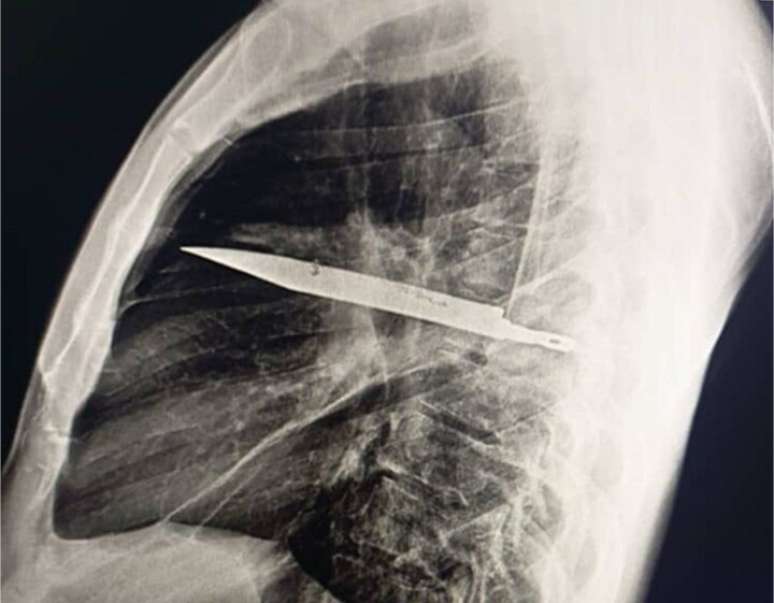

Foto: Reprodução/Biblioteca Nacional de Medicina dos Estados Unidos

Durante todos esses anos, o homem não apresentou sintomas. Somente quando a secreção surgiu é que procurou atendimento e os médicos decidiram realizar exames de imagem -- e a radiografia revelou a lâmina atravessada no peito, sem atingir órgãos vitais.